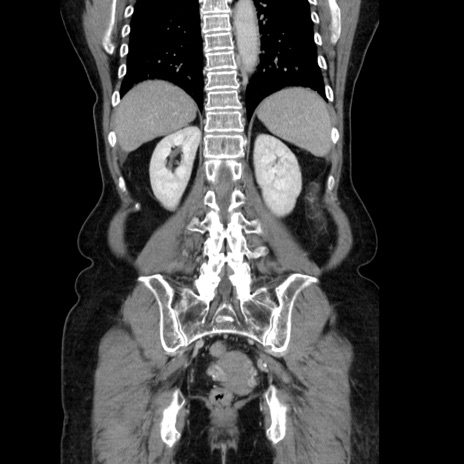

症例5(冠状断像)

【症例】70歳代女性

【主訴】お腹が張る

【現病歴】1週間くらい前から腹部膨満の自覚あり。昨日夜から増悪したため、本日救急外来受診。

【身体所見】意識清明、BT 36.5℃、BP 165/106mmHg、HR 80bpm、SpO2 98%、腹部:膨満、軟、自発痛・圧痛なし、触診にて不快感あり、腸蠕動音:減弱

【データ】WBC 12600、CRP 1.04